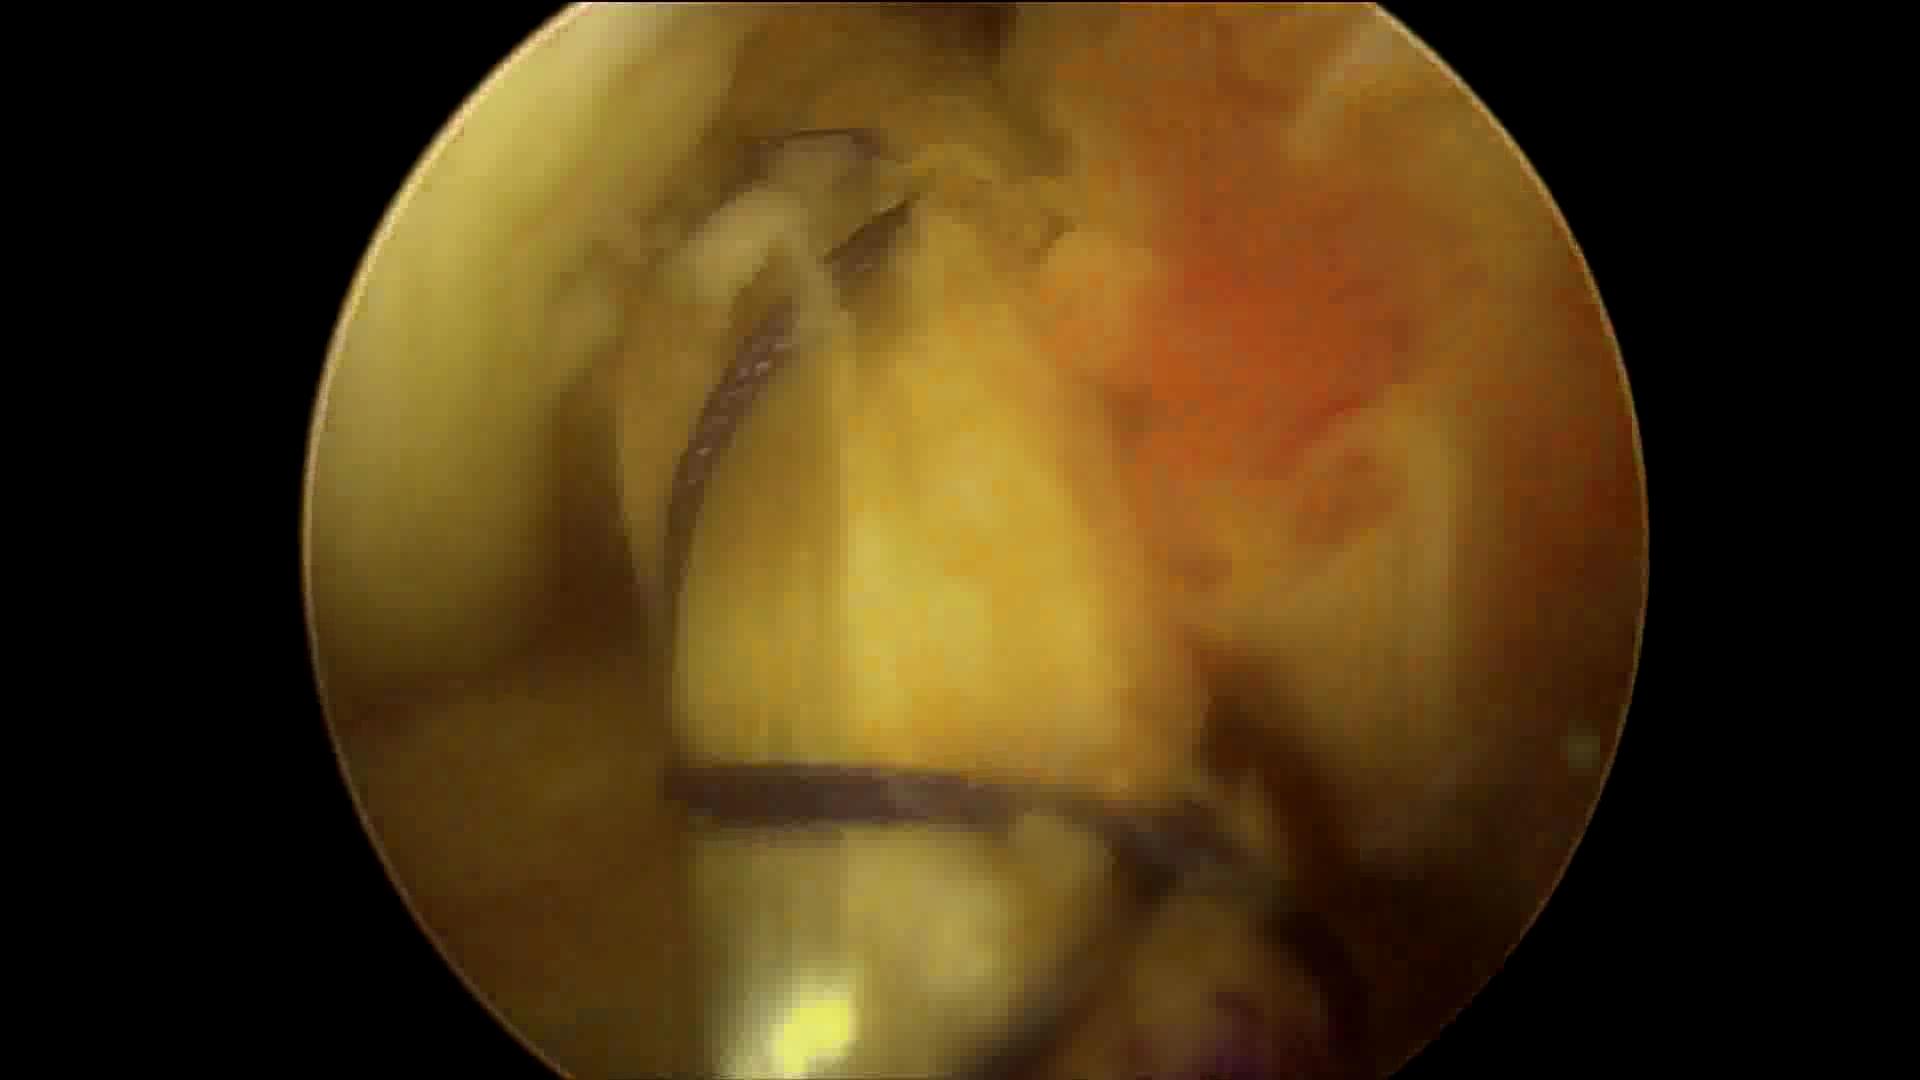

重建的前交叉韧带

因此,保残重建也是现在主流的手术方式!